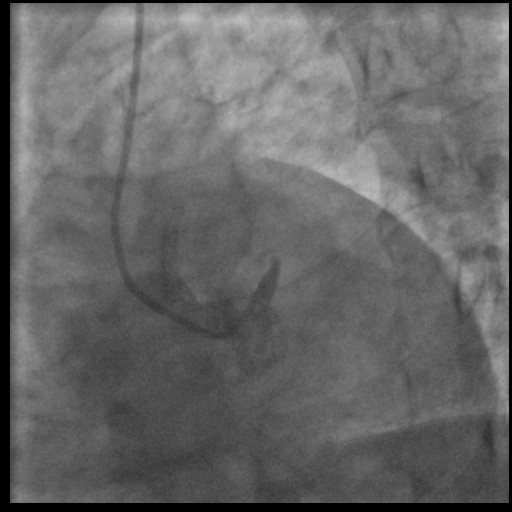

We immediately activated the Cath-lab and did the Primary PCI. We used radial access and 6F sheath, and the using Tig-5F catheter, we cannulated RCA and LCA. The culprit lesion was in the left main artery and a TIMI flow 0. RCA had a good TIMI flow, with borderline lesion in proximal to mid part.

LCA1.avi

LCA2.avi

RCA.avi